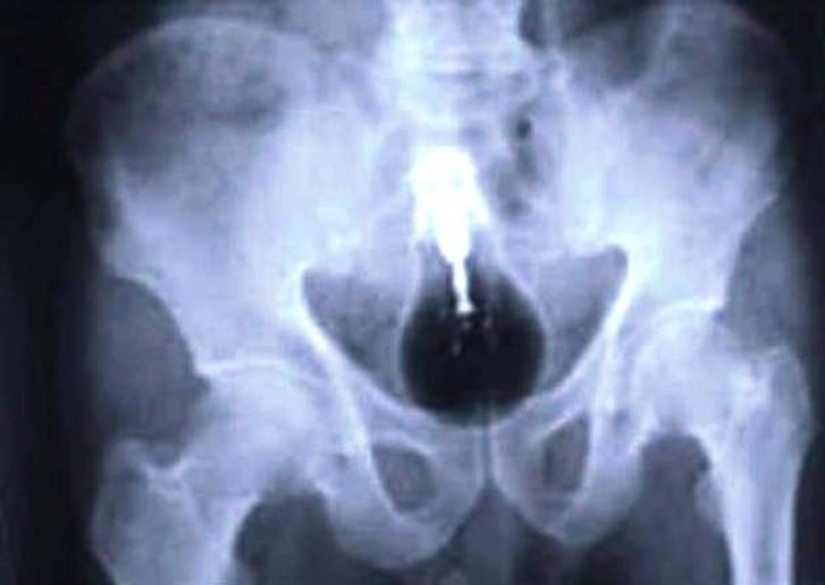

8. Handle.